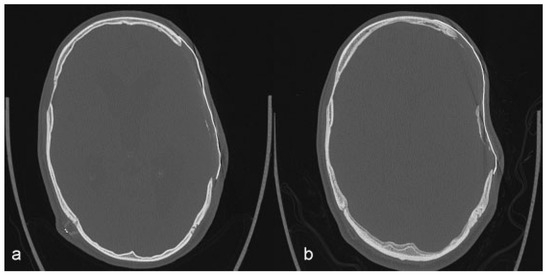

De Water, V.R.; dos Santos Rubio, E.J.; Schouten, J.W.; Koudstaal, M.J. Deformation of a Titanium Calvarial Implant following Trauma: A Case Report. Craniomaxillofac. Trauma Reconstr. 2016, 9, 158-161. https://doi.org/10.1055/s-0035-1567810